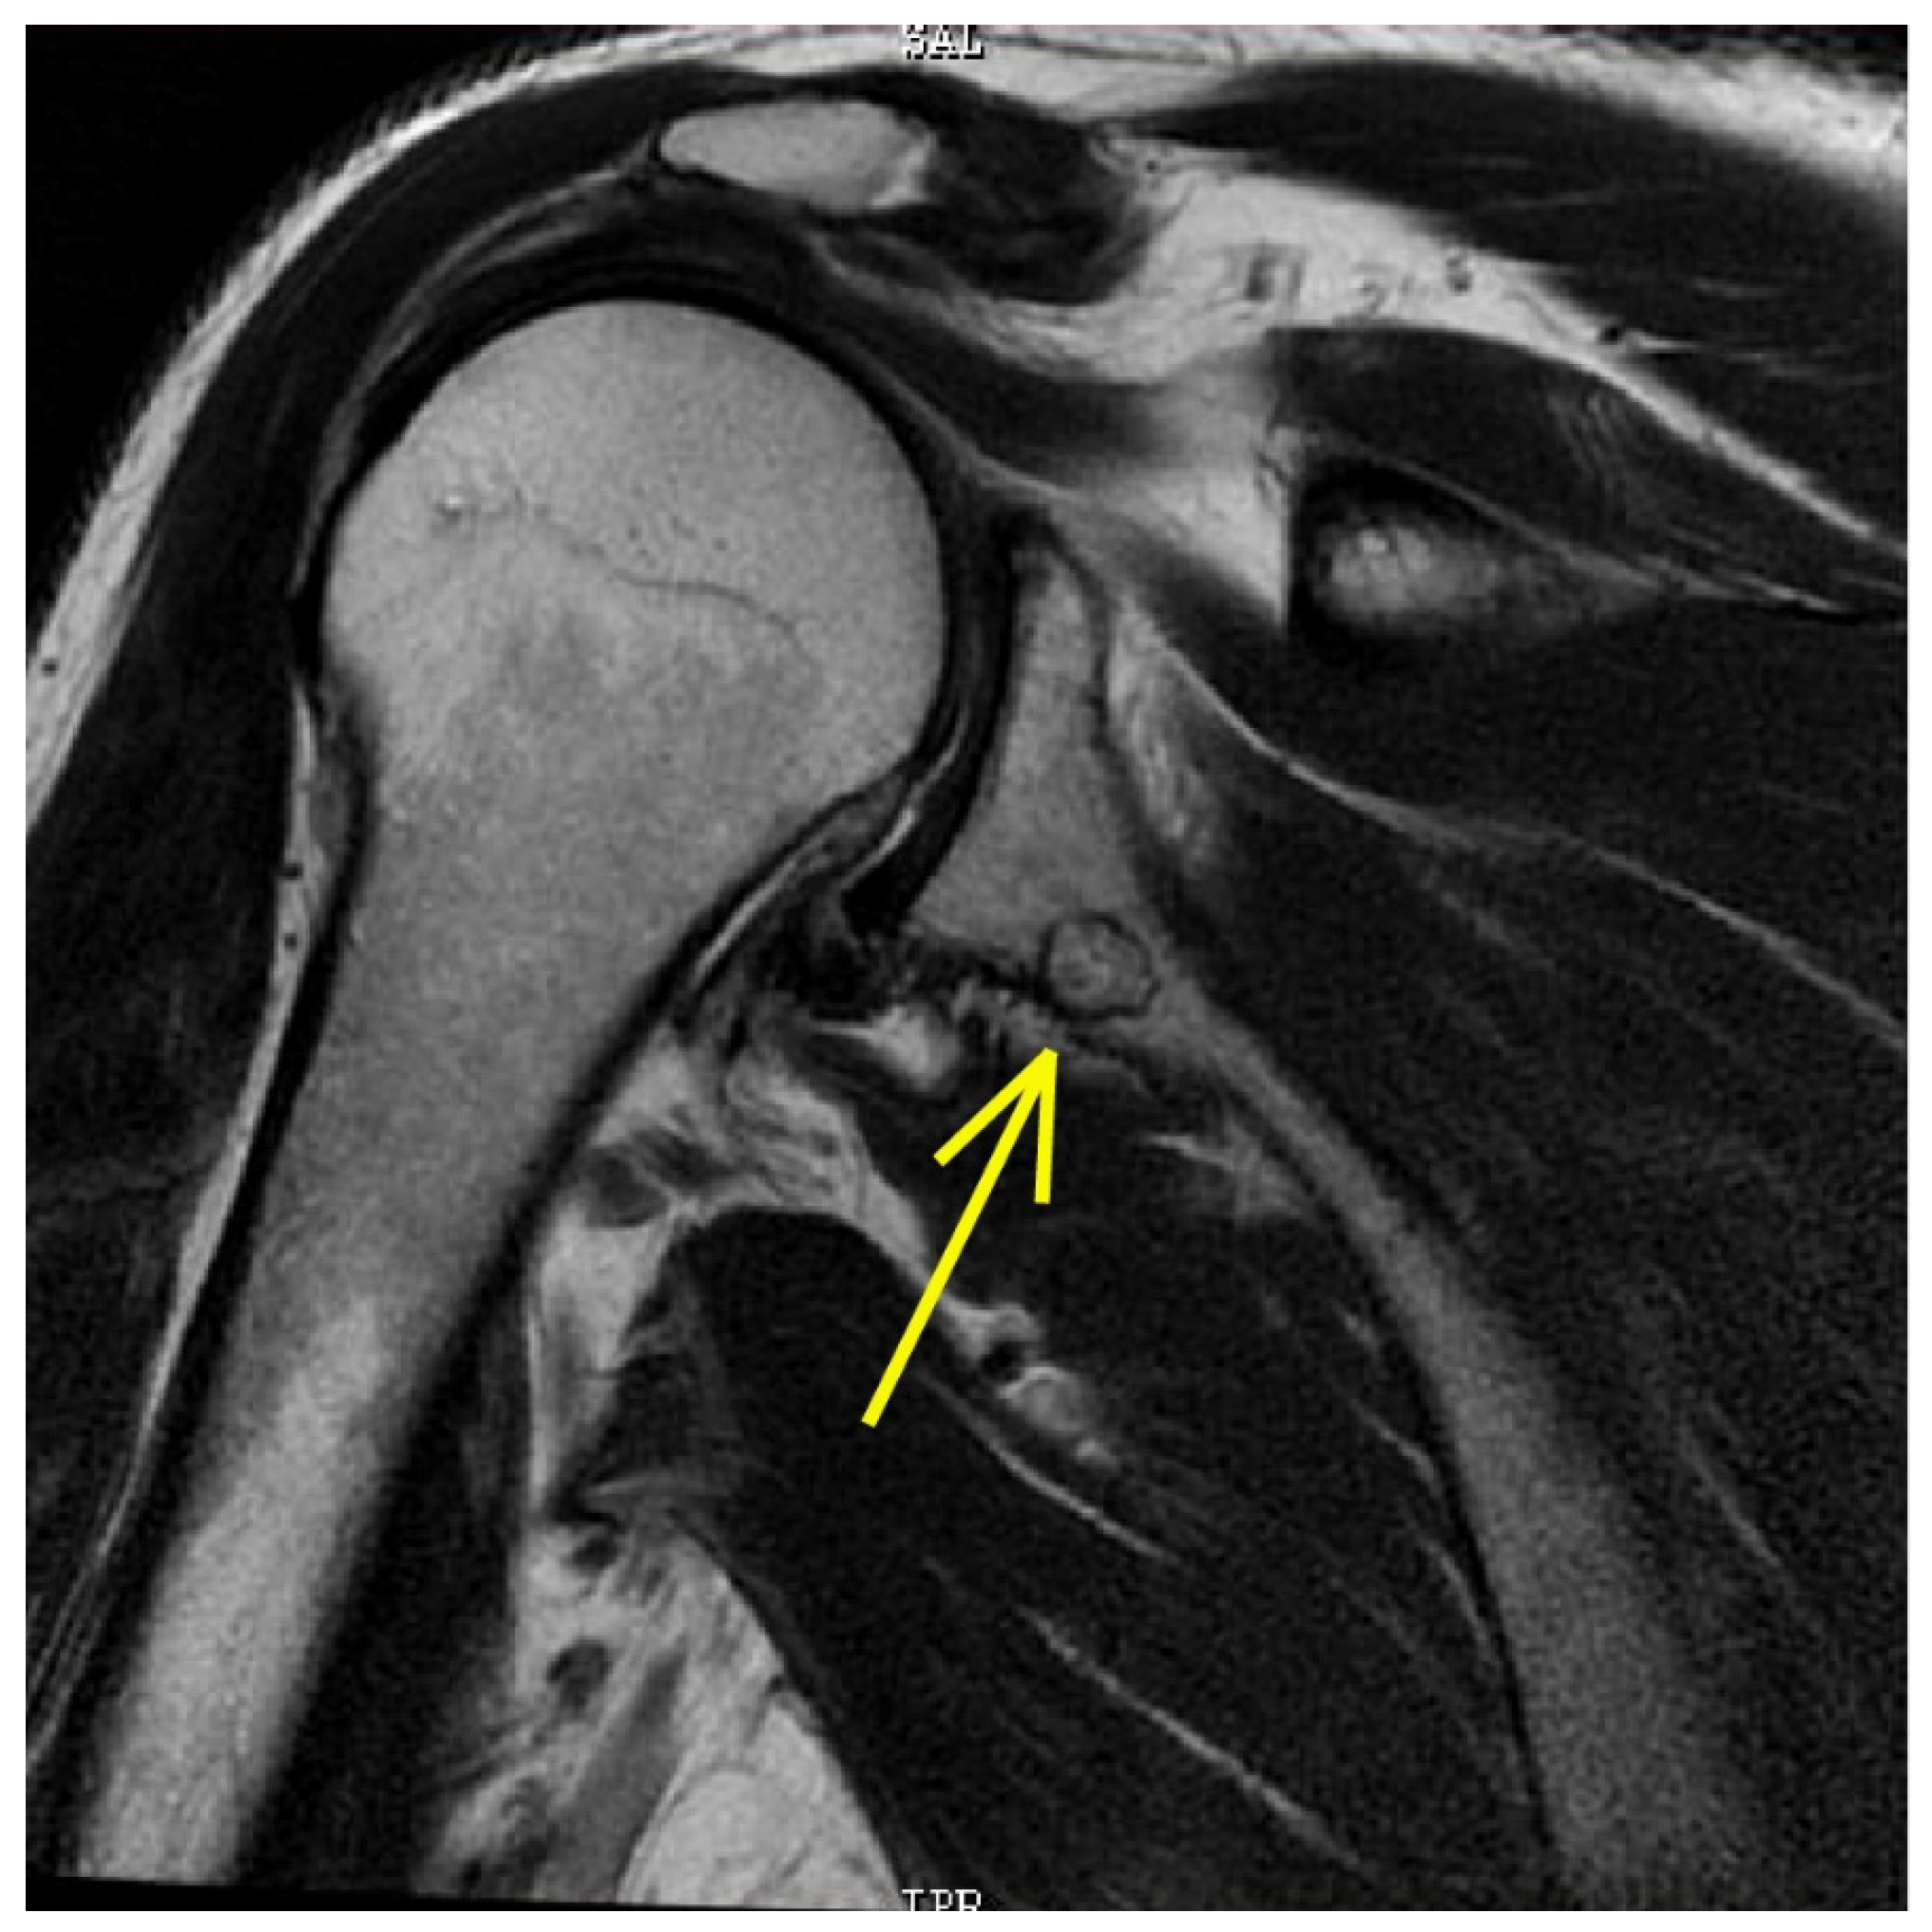

3.2. Imaging